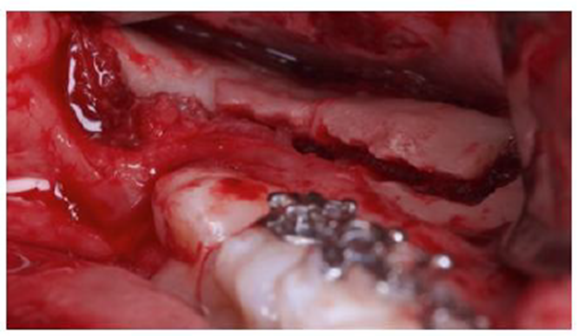

O enxerto ósseo foi colhido no ramo mandibular esquerdo (Figura 4). Uma incisão muco periosteal foi feita com um bisturi número 15C, desde o ramo mandibular até o vestíbulo mandibular pelo primeiro molar. Após o descolamento da mucosa vestibular, também foi descolado a mucosa lingual.

Duas osteotomias verticais e uma horizontal foram realizadas no ramo mandibular com uma broca 701, para que um bloco ósseo pudesse ser colhido para a reconstrução vertical (Figura 5). Após a retirada do enxerto com auxílio de elevador de raiz, o bloco foi cortado em dois pedaços finos com um disco e o osso remanescente fresado, para que pudesse ser utilizado como osso particulado (Figuras 6 a 8).